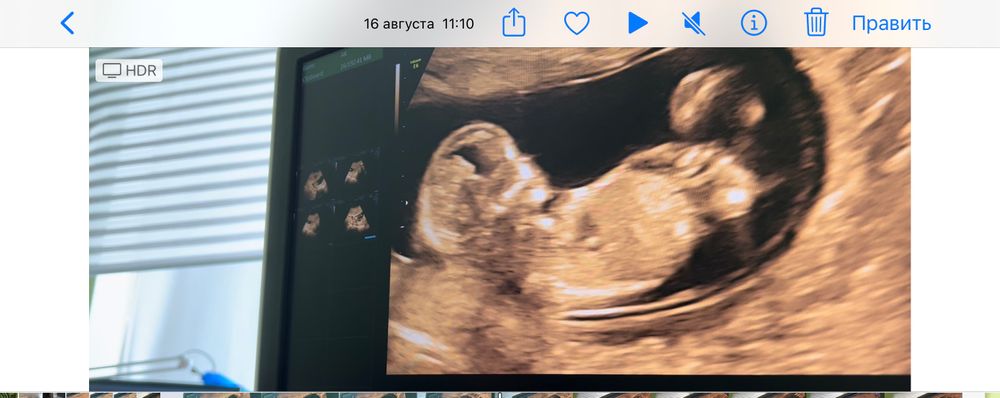

Пол малыша по фото УЗИ 12 недель)

Это девочка )

Наталья, да. У мальчиков он сильнее вверх направлен.

Девочка

Наталья, угол наклона полового бугорка😁

На мальчика похож малышок! Пусть растёт здоровенький!👌🏻🍏☘️

Мальчик😊

На мальчика похож, пусть растет здоровеньким🤗Это у вас ровно 12 неделек?

кажется,там точно мальчик)